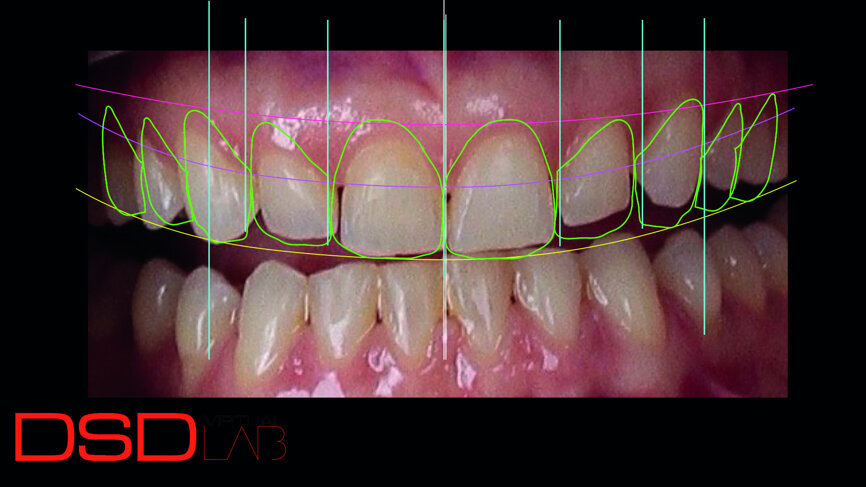

Fig. 3: Digital smile design indicating crown lengthening of teeth #13, 12, 11 and 21 and restorative treatment of the ten anterior teeth

Digital smile design according to Coachman and Calamita9 was performed, from which a treatment plan of crown lengthening and veneers on teeth #15–25 (Fig. 3) was proposed. A conventional diagnostic wax-up was also produced (Fig. 4). Both digital and conventional mockups were applied, and agreement was attained concerning tooth shapes and proportions. Crown lengthening was performed, guided by the digital mock-up, with the use of an acrylic transparent double crown lengthening guide that indicated the borders of the gingivectomy and alveolectomy needed in periodontal surgery for aesthetic rehabilitation (Figs. 5 & 6). [10]